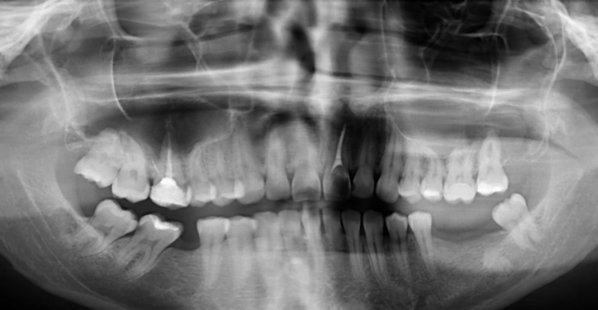

Полгода назад, у меня выпала пломба на 4 жевательном зубе сверху с левой стороны. Все это время он не беспокоил, а потом стал побаливать.

Обратилась к стоматологу пару дней спустя, после того как начал побаливать. Он распломбировал и почистил каналы, оставил зуб открытым, чтобы ушло воспаление. Сказал полоскать содо-солевым раствором. Первые дни ужасно сильно болело, еще два дня боль постепенно шла на спад. Пришла на повторный прием. Он заложил лекарство и закрыл временной пломбой. Назначил прием через два дня. Зуб вообще не болел.

Когда снова пришла, он запломбировал каналы и поставил пломбу. И уже третий день подряд болит зуб. То сильная боль, то терпимая. Перепадами. Когда уже не могу терпеть, пью обезболивающие. Еще принимаю противовоспалительные.

Конечно, при постоянной пломбировке зуб беспокоить уже не должен. Судя по методам лечения, у вас обострение хронического периодонтита, но оставлять открытым канал на полоскание нельзя, это неграмотное лечение. А также беспокойство зуба, возможно, связано с недолеченным процессом хронического воспаления, обратитесь к другому стоматологу на лечение данного зуба.